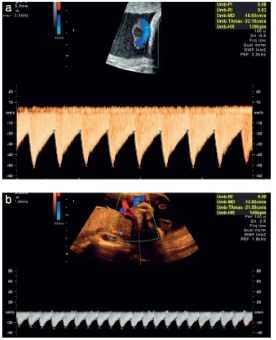

Рис.5. Цветовое картирование Виллизиева круга.

- С помощью цветного допплера определяем Виллизиев круг и проксимальный отдел средней мозговой артерии (рис.5)

- Контрольный объем должен быть размещен в проксимальной трети CМA, около места отхождения со внутренней сонной артерией, поскольку систолическая скорость уменьшается с расстоянием от места отхождения данной артерии.

- Угол между ультразвуковой волной и направлением потока крови следует держать как можно ближе к 0 ° (рис. 6).

Рис.7. Запись допплерографии в венозном протоке без коррекции угла. Низкая скорость фильтра стенки сосуда (стрелка) не влияет на а-волну (а) и далека от базальной линии. Высокая скорость развертки позволяет детально визуализировать изменения скорости.

Рис.8. Запись кривой кровотока в венозном протоке в 36 недель с повышенной частотой (а). Препятствия в виде дополнений повышенной эхогенности вдоль базальной линии приводят к усложненной дифференциации реверсного потока крови (стрелки). (b) повторная запись с небольшим увеличением низкочастотного фильтра стенки сосуда (стрелка) улучшает качество и позволяет четко визуализировать реверсный кровоток (стрелки).